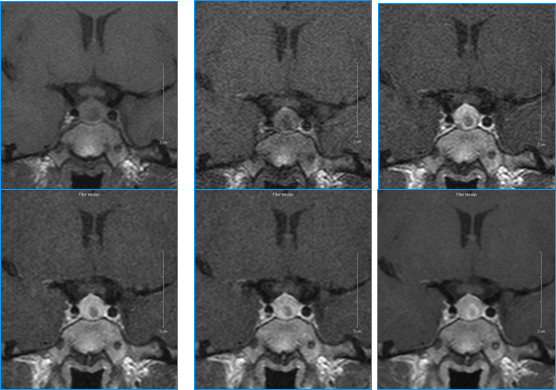

( 6 )磁共振椎管造影: MRM 能够显示椎间盘或骨赘与神经根鞘膜、尾丝之间的空间关系同时,它还可以为外科医生提供一种线路图